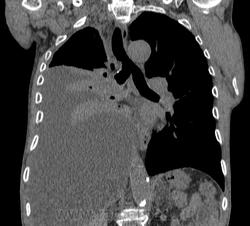

Пожилой мужчина, лечился по н/д правостороннней пневмонии в терап/отделении. Жалобы на одышку, кашель. По результатам Р-контроля после лечения направлен на КТ легких с диагнозом: плеврит справа, распад? В корне правого легкого вижу объёмное образование, с распадом. Смущают размеры плеврита,очень много жидкости, почти до 3 ребра. Анализы крови спокойные- L4,0-6,6, СОЭ 12-16мм. Неужто ТБС, отсев бы был при таком огромном поражении. В посеве мокроты-100% высев клебсиэллы пневмоние. Мокрота на общий анализ в работе-собирает с трудом, изза отсутствия мокроты. Плевральную пункцию еще не проводили. Н азначила бронхоскопию и плеврал пункцию. Как думаете, уважаемые коллеги, это онкопроцесс или тбс распад?

Самое интересное забыла показать- может это 100% навеет на мысль об опухолевом процессе, остеолитическая деструкция позвонка?

Не смотря дайкомы, только по рентгенограмме, предположил бы центральный рак правого легкого. Потому что большой гидроторакс, без смещения средостения в здоровую сторону, как правило, соответствует раковому ателектазу.

Коллеги, распада там нет, это вас медиастинальное окно подвело. В грудине тоже все в порядке. Да и компрессия позвонка "старая".

Рак.

Небольшое количество увеличенных лимфоузлов, и те - не сказать, чтоб были очень крупными. От эмпиемы до онкологии... Умеренное количество жидкости в перикарде, толщиной слоя до 13-14 мм. При подобной картине не вижу смысла гадать по сжатому лёгкому, пишу так: массивный выпот справа, около 2500 мл, диафрагма оттеснена жидкостью каудально, печень (!!!) смещена каудально и вправо. Легкое справа значительно компрессировано жидкостью, оценка проходимости бронхов и состояния легочной паренхимы (кроме имеющейся эмфиземы) практически невозможна. Необходима пункция плевральной полости справа (цитология, ВК, посев на микрофлору и проч), КТ-контроль после эвакуации жидкости.